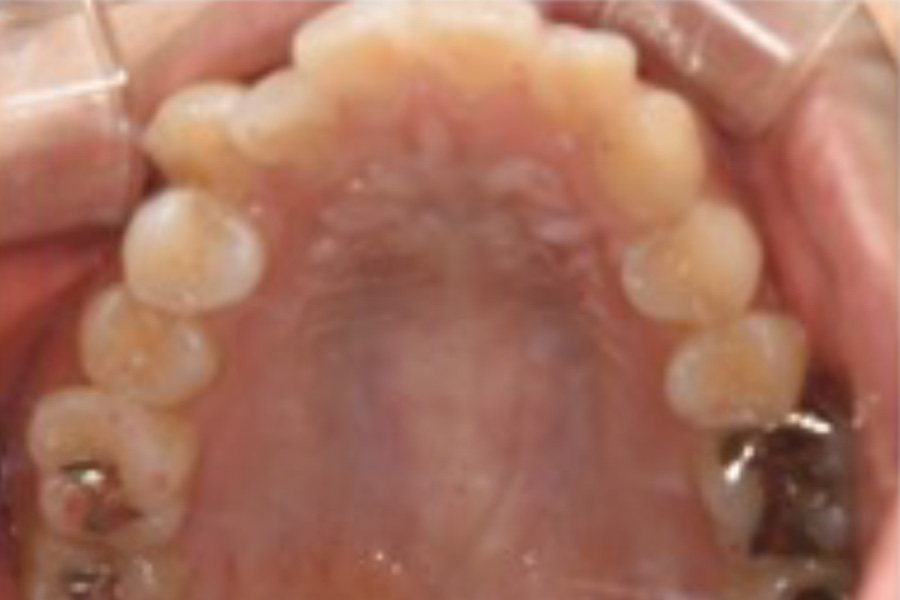

治療後

主訴 右上が気になる。下顎の歯並びを治したい。

治療内容 目立ちにくいマウスピース矯正(非抜歯矯正)

歯と歯の間に隙間をつくることにより、歯列弓を広げながら治療を行いました。